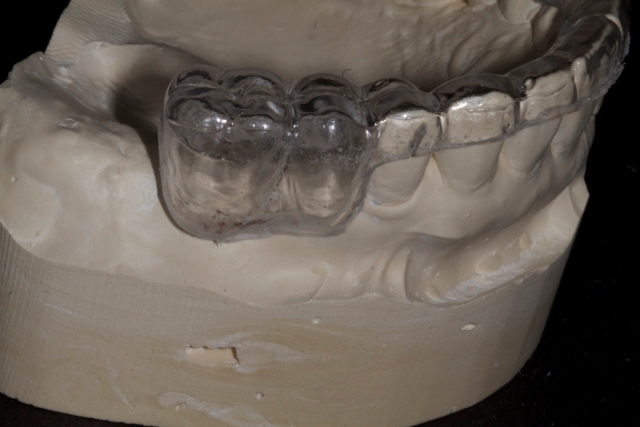

4. The appliance should then be trimmed so that the desired gingival levels of the final restorations are intact. The remaining teeth should be trimmed back so that 1-2 mm of overlapping acrylic remains to stabilize the template. This is an important landmark for the surgeon.

5. Using a radiopaque self-curing methylmethacrylate mixed to a putty consistency, fill the space left by the denture teeth or wax-up.

6. Trim the excess acylic back to the gingival margins.

10. When tried in, the template should be solid and stable and have a “snap-fit.”

The patient can be instructed in how to insert the appliance and can take it with them if they are having the CBCT done outside of your office. The end result will give you and the surgeon a more clear understanding of potential implant positions. The hole that is drilled through the teeth will be radiolucent on the CBCT and serve as an indicator of possible implant angulation that can be corrected by the surgeon as the case is planned.